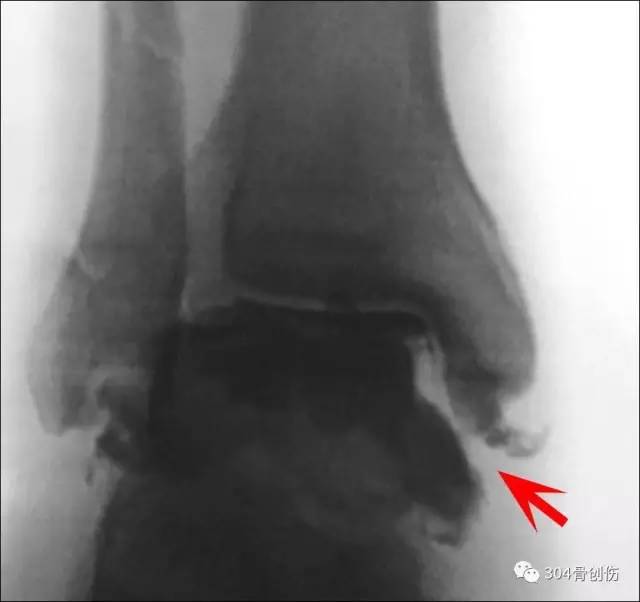

X 线诊断

目前国内外对下胫腓联合分离的 X线诊断标准较多,尚无定论。

多数认为X线片正常下胫腓解剖关系如下:

①前后位或踝穴位片上下胫腓骨间隙≤5mm;

②前后位片上胫腓骨重叠>6mm或大于腓骨宽度的42%;

③踝穴位片上胫腓骨重叠影>1cm;

若超过上述范围,则认为损伤或分离。Rose等认为在没有腓骨骨折的情况下,踝关节内侧间隙增宽是判断下胫腓联合分离最可靠的 X线表现。

踝穴位X线片测量

在普通X线检查阴性时,应摄距小腿关节外展外旋应力位像,以发现隐匿的下胫腓联合分离。但也有作者认为应力位摄片对诊断无帮助。